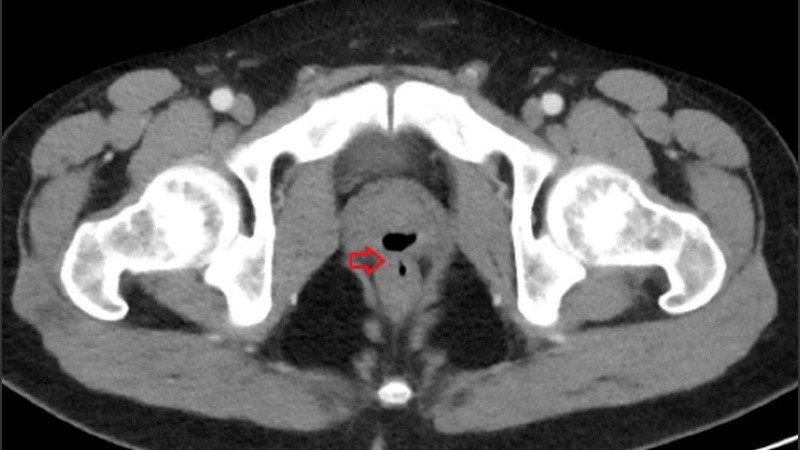

El equipo médico resolvió hacerle una tomografía y un cistouretrograma miccional de la pelvis, es decir un examen en el que se hacen rayos X de la vejiga y del tracto urinario.

Por un lado, los especialistas detectaron infección en el tracto urinario, inconvenientes en la pared rectal y algo un poco inquietante: una “fístula rectal-prostática”.

En otras palabras, observaron una especie de “pasaje” anormal entre la uretra y el recto. A través de él estaban pasando algunos líquidos y sólidos.